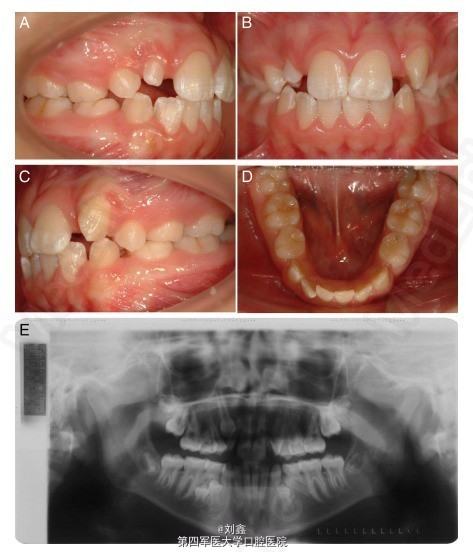

该患者为未成年女性,13 岁,因牙列不齐,影响美观要求正畸治疗。通过对患者的临床检查和曲面断层照片检查,发现患者上颌 15、22、25、35 牙齿尚未发育完全,12 牙齿发育过小;咬合关系和上下颌骨关系正常(图 1)。 根据患者的具体情况,制定详细的治疗计划。首先应用固定矫治器将 14 和 24 移向远中(图 2 A-D),13 随后萌出。21 和 23 之间的空间也被打开。依据 CT 三维影像确定移植位点牙齿的准确数据,考虑到 45 的大小、牙根的发育程度等情况,选择将 45 拔出后移植至 22 的位置。手术预备移植位点的牙槽窝 (图 2E,F)。 拔出 45,移植入预备好的 22 牙槽窝(图 3A-F)。缝合伤口,术后用树脂将 45 与邻牙固定两个月,四个月后开始移动 45(图 3G,H)。 该病例整个治疗过程持续 32 个月,治疗结束时临床和影像学检查显示,移植的前磨牙外形美观,牙根发育已完成,根管也已完全闭锁,预后良好(图 4A-E)。